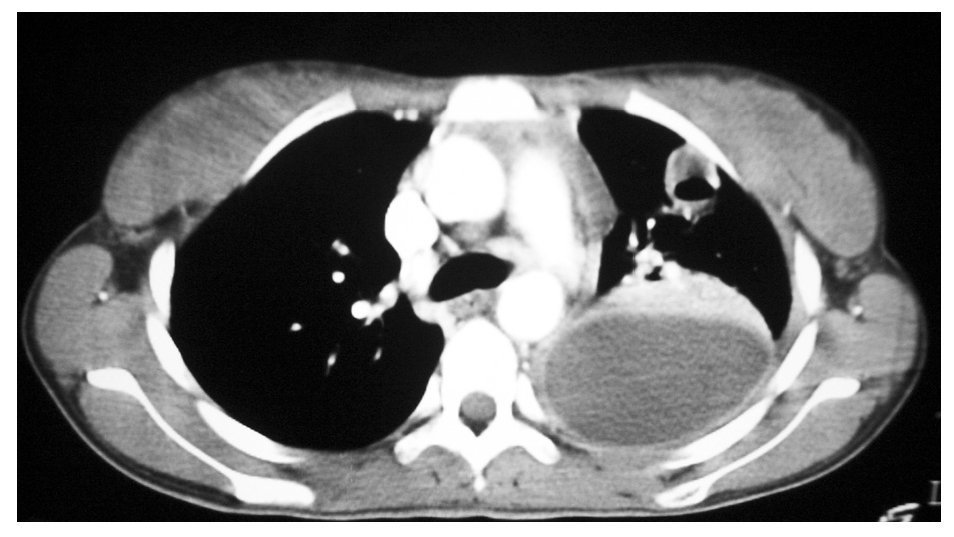

Fig. 3. Tomografía computarizada de tórax.

Se realizaron pruebas de imagen consistentes en radiografía simple de tórax y senos paranasales, tomografía computarizada de tórax, ecografía abdominal y ecografía doppler cervical.